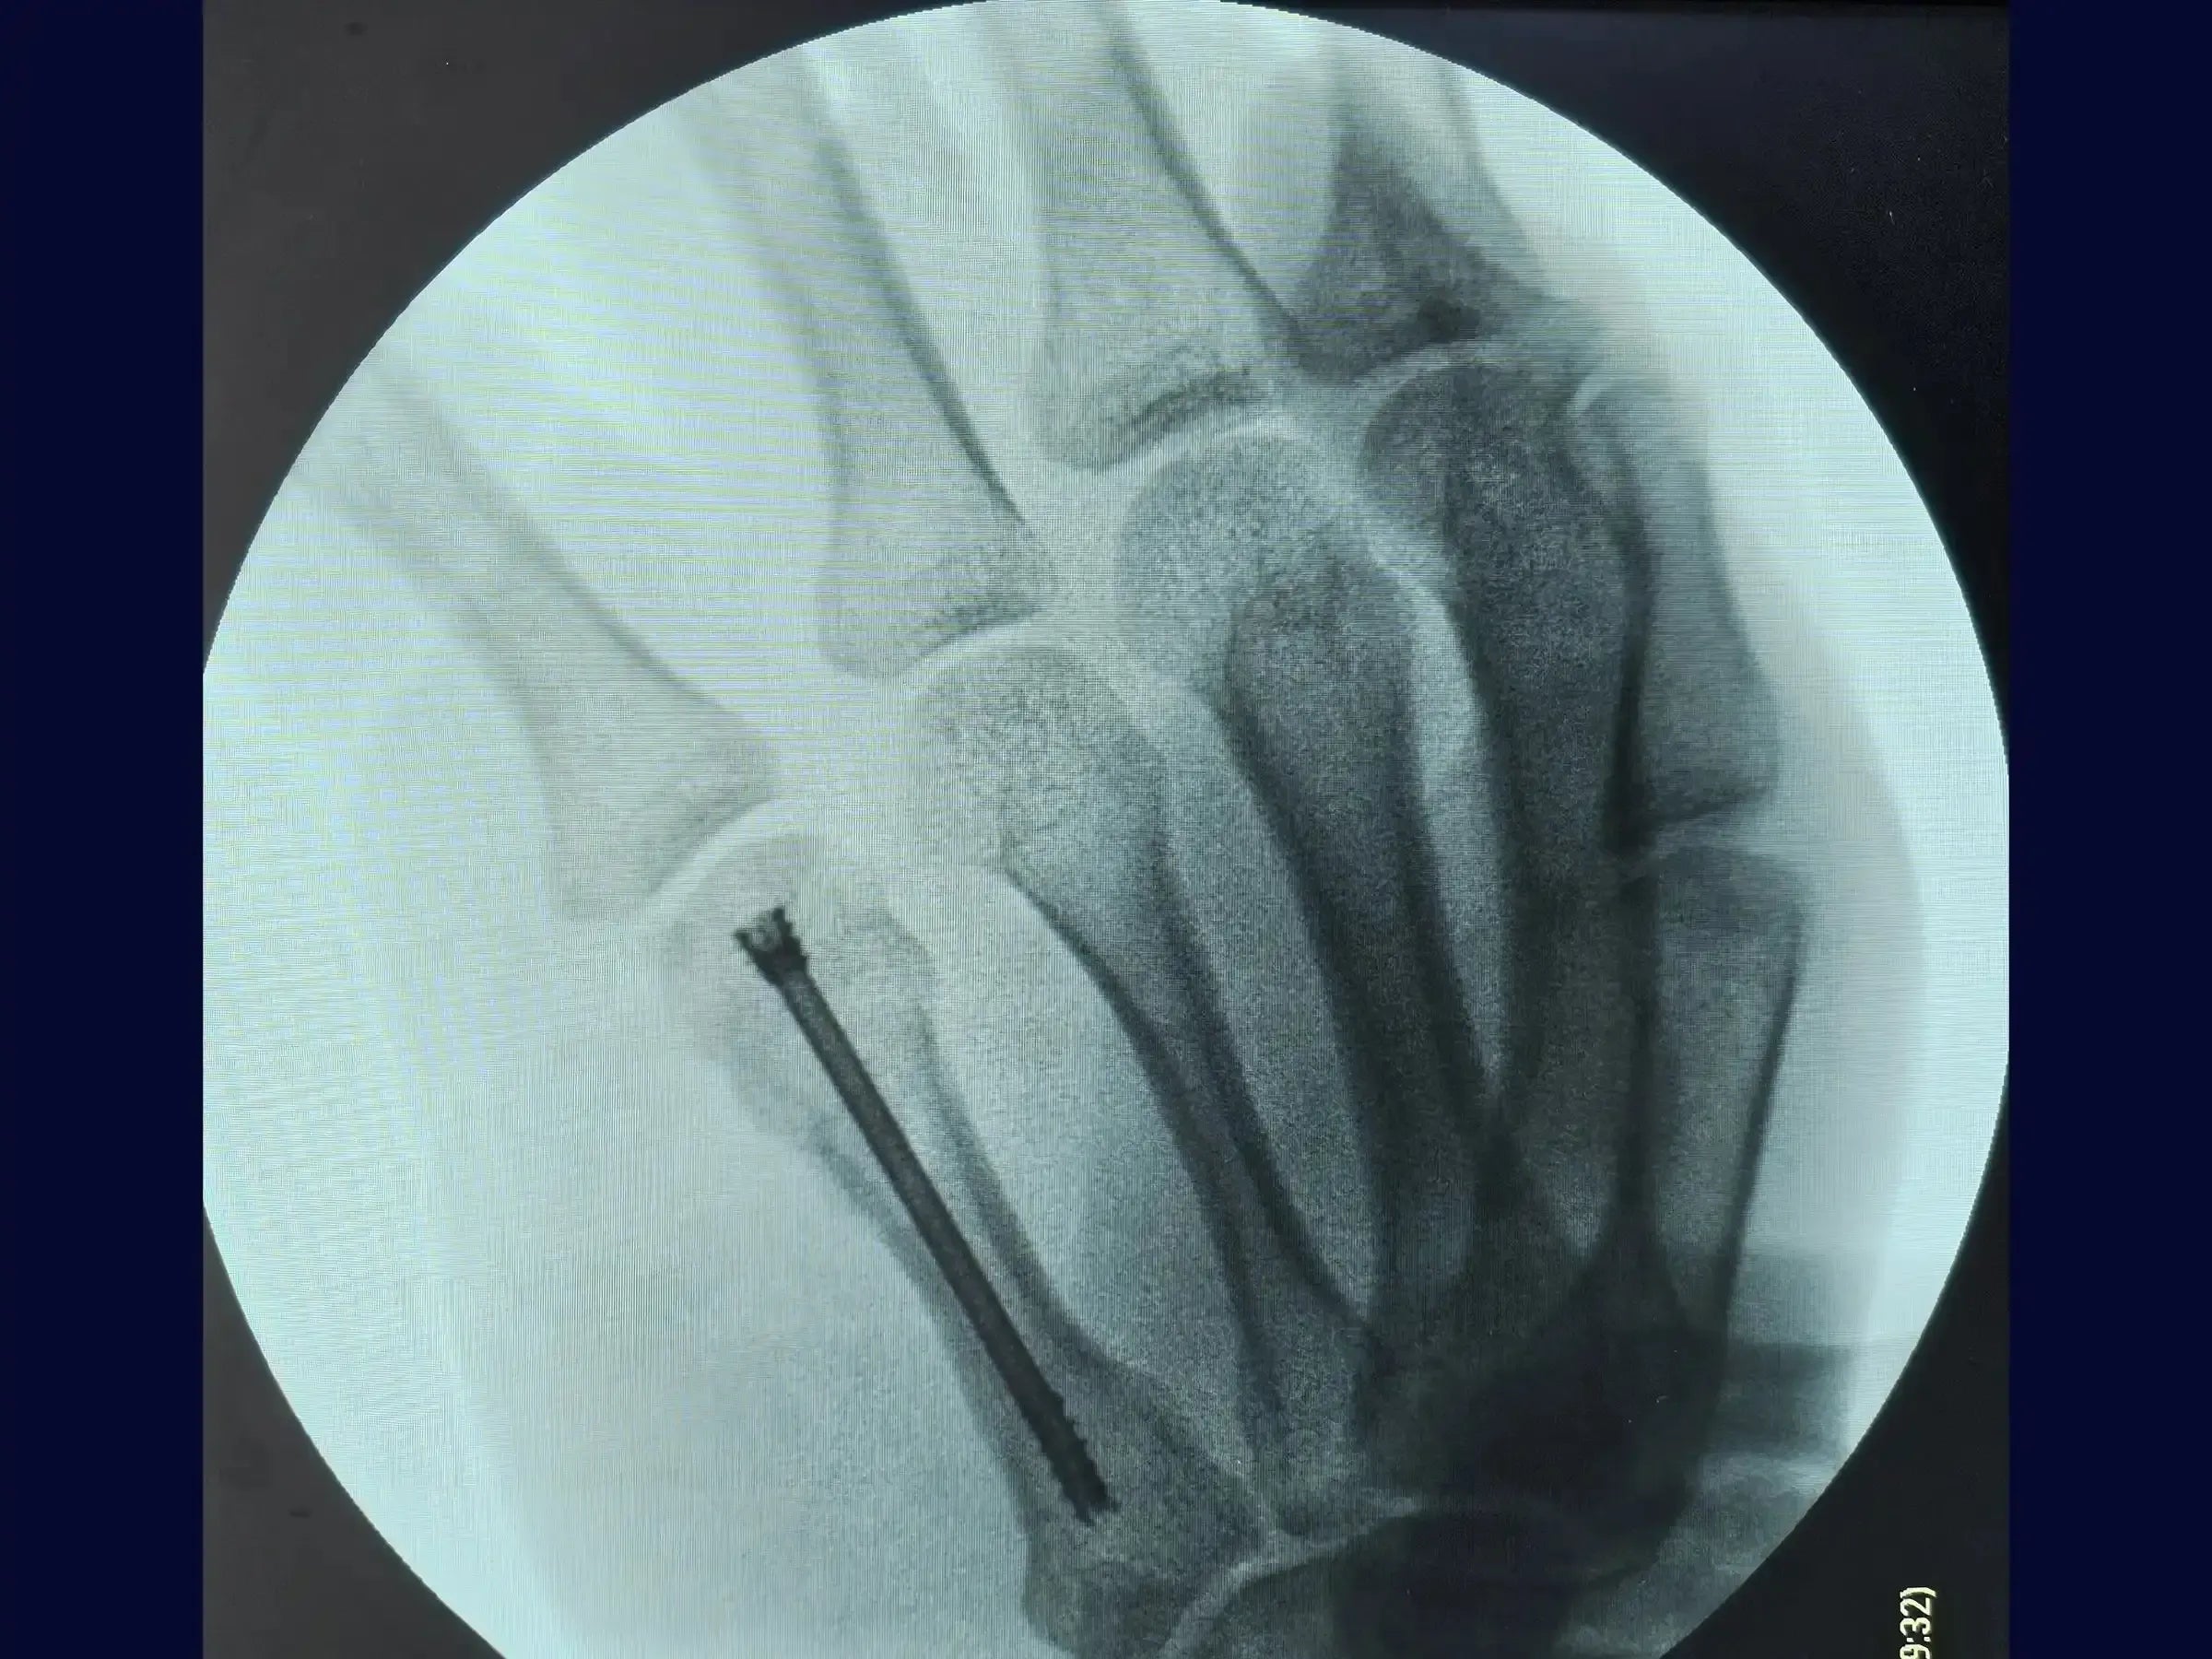

- Inserción de Tornillo de Doble Compresión: Dominar la técnica de inserción del tornillo de doble compresión a través de la guía, siguiendo las pautas establecidas en manuales como el AO.

- Confirmación final y recuperación acelerada: Comprenda los criterios para la confirmación final de la fractura reducida y la colocación del tornillo extraarticular. La técnica mínimamente invasiva garantiza una recuperación muy satisfactoria, evitando incisiones cutáneas extensas y abordajes más agresivos, con un cierre cutáneo realizado con solo dos puntos.